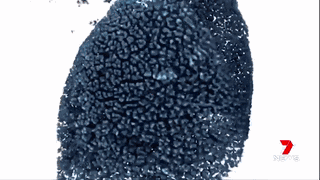

胰腺癌治療

胰腺癌是最耐藥的病癥,已經(jīng)成為澳洲最致命的病癥。大多數(shù)被診斷為胰腺癌的病人會(huì)在半年內(nèi)死亡。

澳洲的科學(xué)家們通過運(yùn)用納米技術(shù),將“基因沉默”(gene silencing)藥物運(yùn)送至腫瘤細(xì)胞中來治療胰腺癌。

藥物已經(jīng)在擁有和人類相仿的瘢痕組織的小鼠身上進(jìn)行試驗(yàn),并獲得成功。